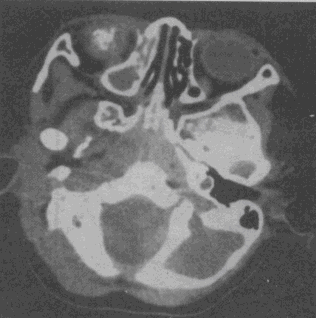

女性,14个月。发现视力低下CT如图所示,最可能的诊断是 YZ332_1_46_17.gif YZ332_1_46_17_1.gif

• A.脉络膜黑色素瘤

• B.视神经胶质瘤

• C.海绵状血管瘤

• D.视网膜母细胞瘤

• E.眼底出血